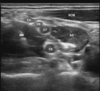

Q

Identify the BLOCK and the structures

A

Interscalene Block